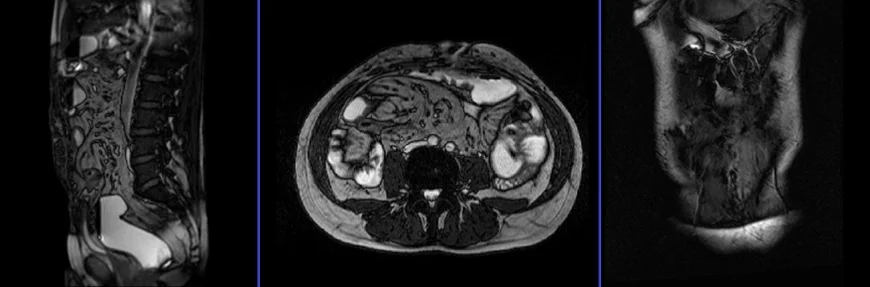

Abdominal Wall MRI localiser

A three-plane T2 TrueFISP/HASTE localizer must be taken initially to localize and plan the sequences. These are fast single-shot localizers with under 25s acquisition time, which are excellent for localizing abdominal structures.

T2 TRUEFISP\HASTE coronal 4mm large FOV

Plan the coronal slices on the axial image, positioning the block horizontally across the abdomen as shown below. Verify the positioning block in the other two planes. Ensure an appropriate angle is set in the sagittal plane, vertically across the abdomen. The slices should adequately cover the entire abdomen from the anterior abdominal wall to the spinal canal. The field of view (FOV) must be large enough to encompass the abdomen and pelvis, from the stomach to the pubic symphysis. To prevent wrap-around artifacts, utilize phase oversampling. Instruct the patient to hold their breath during image acquisition.

T2 TRUEFISP\HASTE axial 4MM Large FOV

Plan the axial slices on the coronal image, positioning the block horizontally across the abdomen as shown below. Check the positioning block in the other two planes. Ensure an appropriate angle is set in the sagittal plane, horizontally across the abdomen. Slices must be sufficient to cover the whole abdomen and pelvis from the stomach superiorly to the pubic symphysis inferiorly. Phase oversampling can be used to avoid wrap-around artifacts. Instruct the patient to hold their breath during image acquisition.